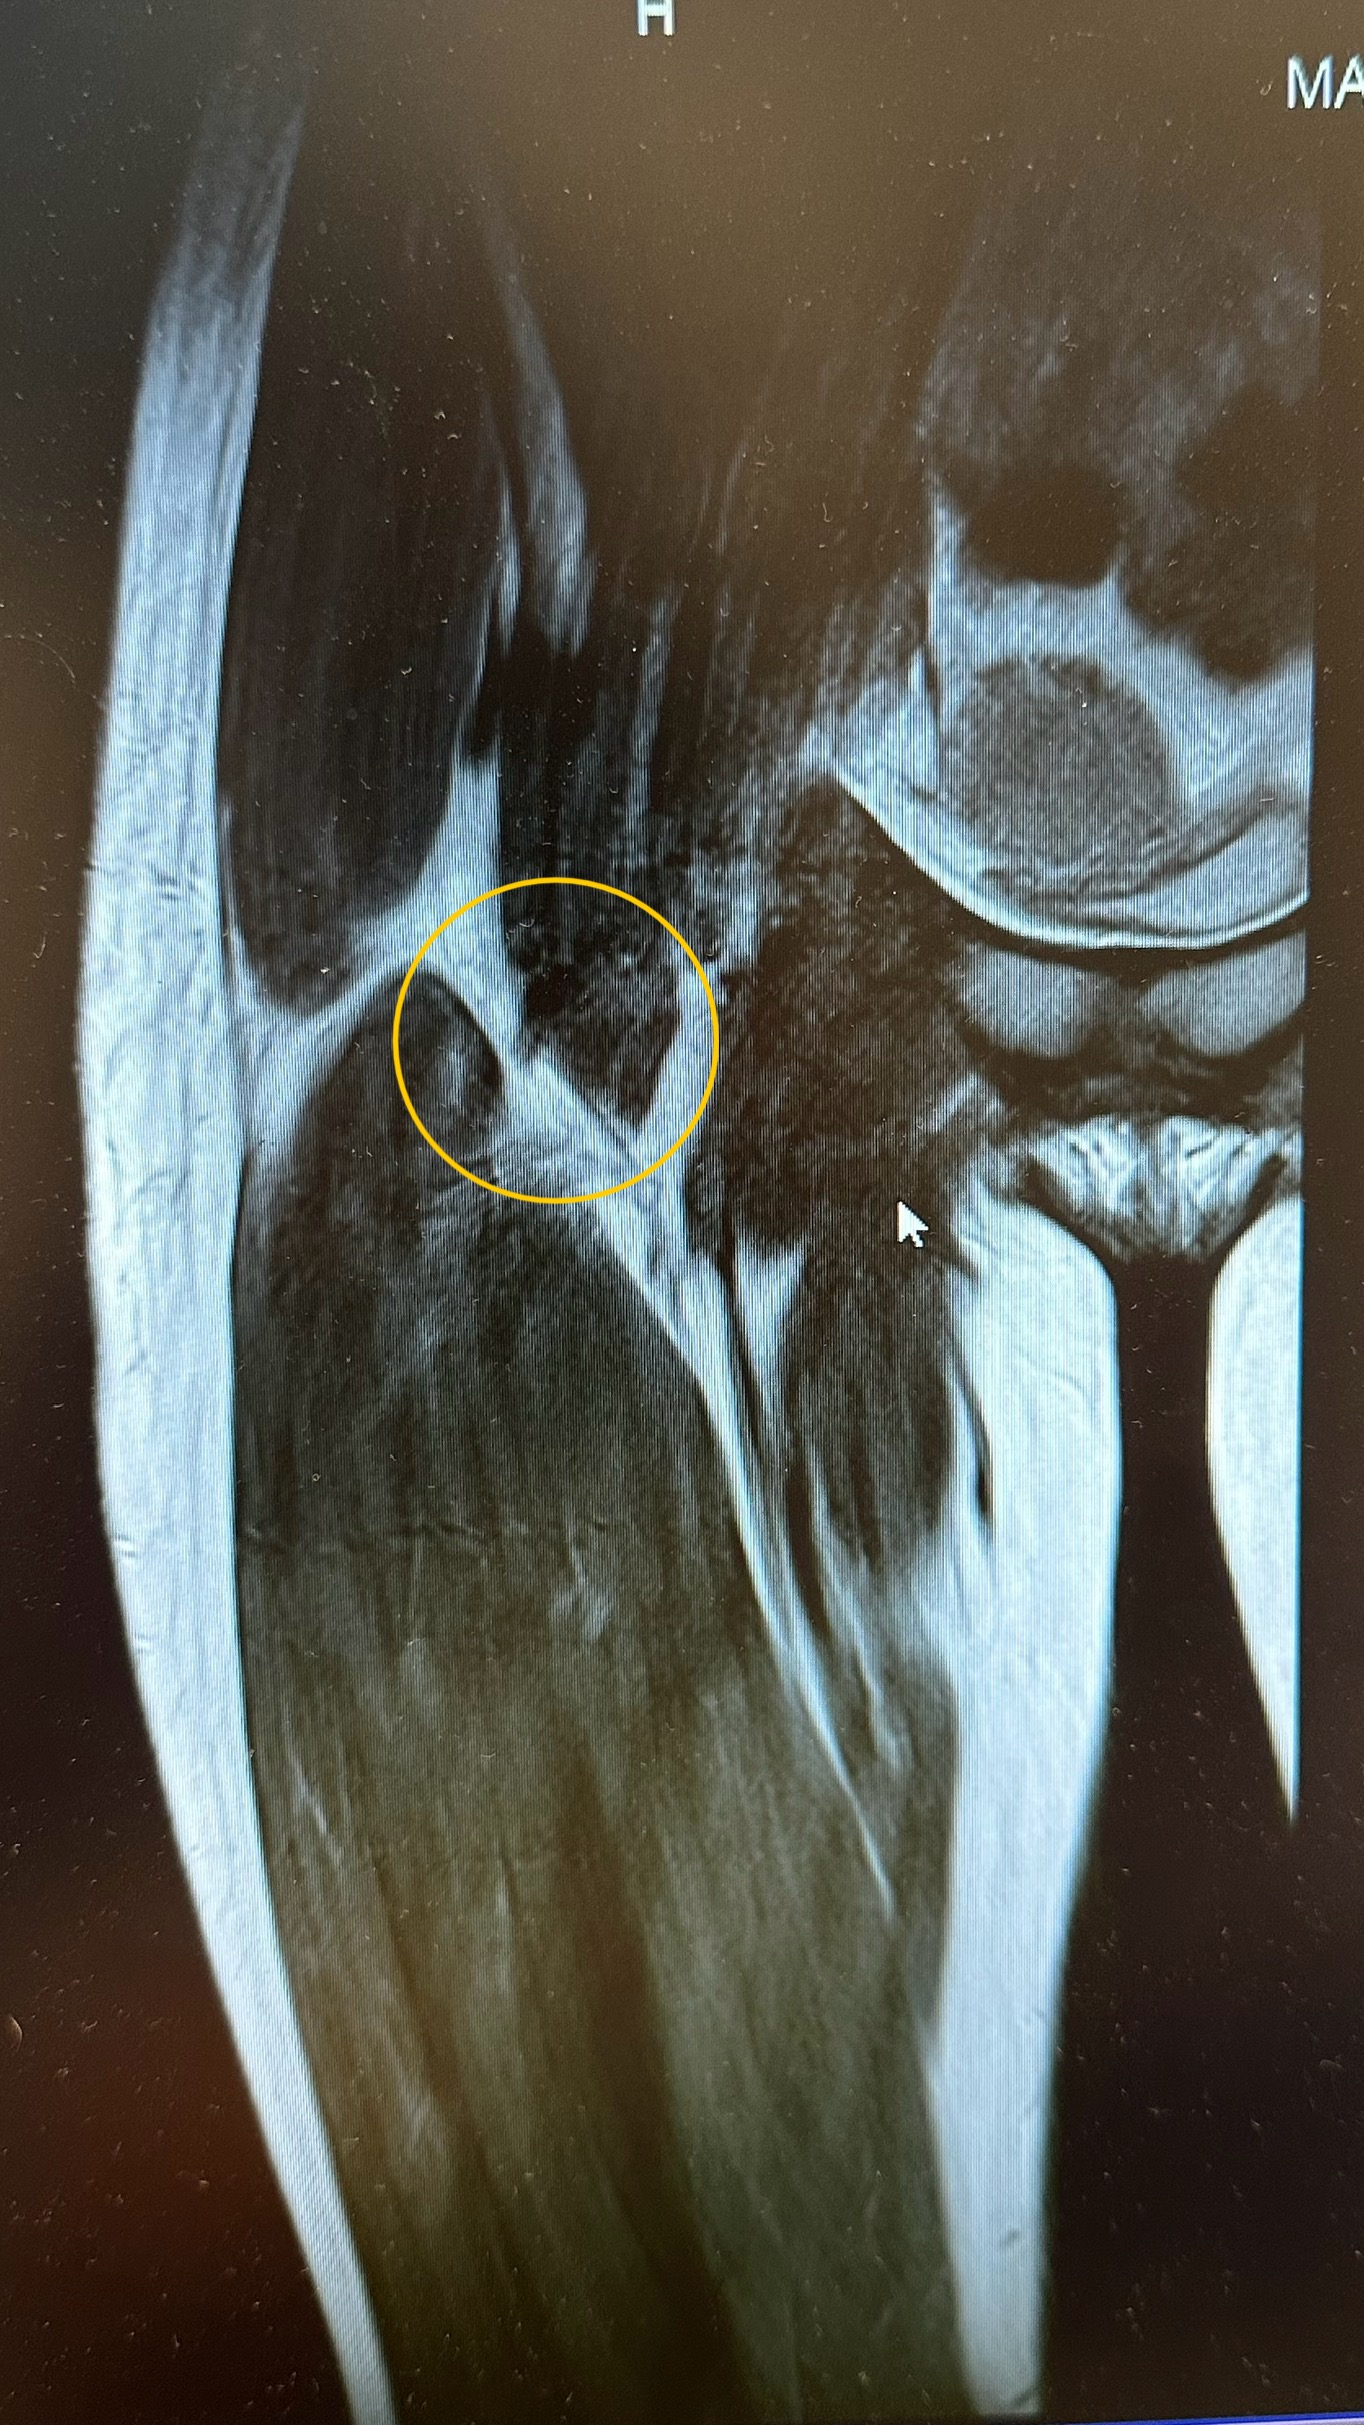

Delna ruptura mišično tetivnega (iliotibialnega) spoja

Anamneza V naši ambulanti Meridian-fit smo obravnavali 17-letno plesalko, ki je zaradi delne rupture iliotibialnega […]